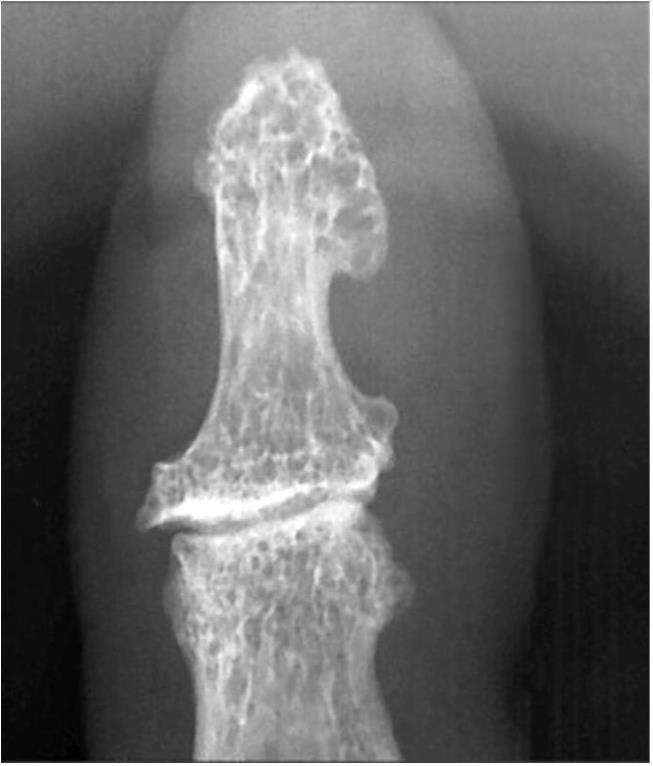

IV стадия — резко выраженная деформация эпифизов, более значительная в суставной впадине, значительное неравномерное сужение суставной щели с возможным разрушением кортикального слоя эпифизов, подвывихами суставов. В IV стадии деформация эпифизов более значительна в суставной впадине. Крупные разрушенные остеофиты окружают суставную поверхность. Расположены остеофиты в основном по тыльным и боковым поверхностям фаланг, в меньшей степени — по ладонной плоскости. Смежные отделы костей склерозированы, с множественной кистовидной перестройкой как по периферии, так и по оси сустава. Суставная щель значительно неравномерно сужена (рис. 9, 10).

Необработанное увеличение: выраженное неравномерное сужение суставной щели разной толщины и расположенный отдельными участками субхондральный склероз, остеофит основания и умеренная кистовидная перестройка головки (см. рис. 10, а); резко выраженный остеофит и крупный отломок остеофита, множественная кистовидная перестройка, неравномерный субхондральный склероз и значительное сужение суставной щели (см. рис. 10, б).

Рис. 10. Рентгенограмма дистального межфалангового сустава III пальца больного IV стадией первичного остеоартроза (5-кратное увеличение рентгеновского изображения) (начало):

а, в — прямая проекция; б, г — боковая проекция. Пояснения в тексте Рентгенограмма дистального межфалангового сустава III пальца больного IV стадией первичного остеоартроза (5-кратное увеличение рентгеновского изображения) (окончание):